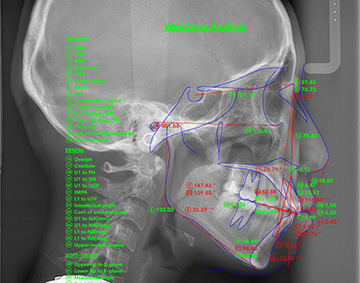

歯科用CT、頭部専用のセファロレントゲン、口腔内スキャナー、歯の移動シミュレーションソフトなど、先進的なデジタル技術を積極的に診療に取り入れています。診断の精度を高め、納得いただける安全性の高い矯正治療の提供につなげています。さらに、院内には矯正を専門とする専任の歯科技工士が在籍しており、装置の精密な作製や調整をスムーズに行う体制を整えています。

セファロレントゲン